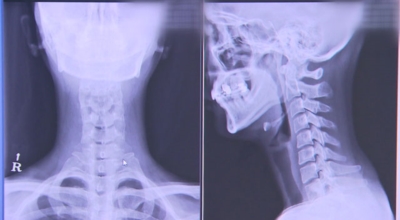

목디스크

경추 사이의 추간판(디스크)이 탈출 또는 파열되어 경추신경이 자극이나 압박을 받아 통증이 생기는 증상을 말해요. 경추는 운동성이 큰 부위로 추간판이 압력을 받으면 튀어나와 척수나 신경을 압박하게 되는데요 목디스크는 퇴행성 변화 이후에 발생되기 때문에 많은 환자들이 만성적인 통증을 지니고 있는 경우가 많습니다.